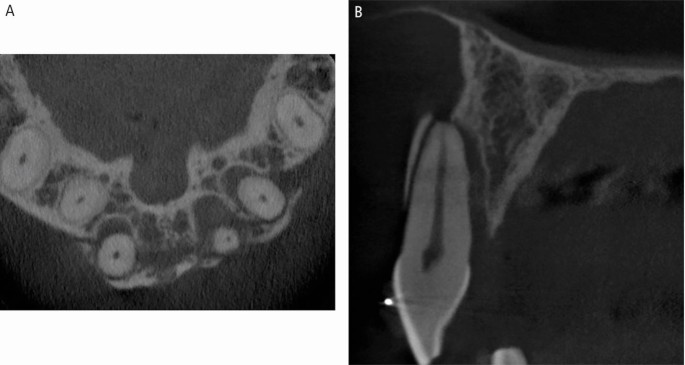

A CBCT scan of a root fracture, seen in the sagittal plane

A CBCT scan of a dento-alveolar fracture extending over three maxillary incisor teeth, seen in the axial (A) and sagittal (B) planes